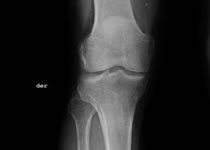

Traumatología y Ortopedia

Cirugia articular:Cadera, rodilla, pie, mano, tobillo, muñeca, cuello, columna vertebral, cervicales, lumbares, ciatica, artritis, reumatismo, tendon de aquiles, tunel del carpo, clavo para hueso artroscopia avanzada, ortopedia, traumatología

Protesis de rodilla, cadera, hombro, * Recambio articular con prótesis